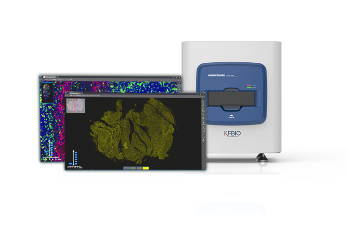

Digital Pathology Slide Scanner (PRO)

Digital Pathology Slide Scanner (PRO)

K-Viewer Download:

K-Viewer, a slide viewing software developed by KFBIO, allows pathologists to review and annotate digital slides for ease of diagnosis. It enables pathologists to swiftly access slides or cases on the desktop or remotely via the computer, smartphone, or tablet device.

To have the most satisfying experience in viewing slides,

please choose the different version of K-Viewer to download.

K-Viewer() for windows xp、7、8、10

KFSlideOS() for 64-bit operating system of windows 7、8、10 (support fluorescence slides)

KFSlideOS() MAC for macOS

Power Up Your Diagnostics

KFBIO telepathology platform helps share medical resources, save time and cost while improving care.